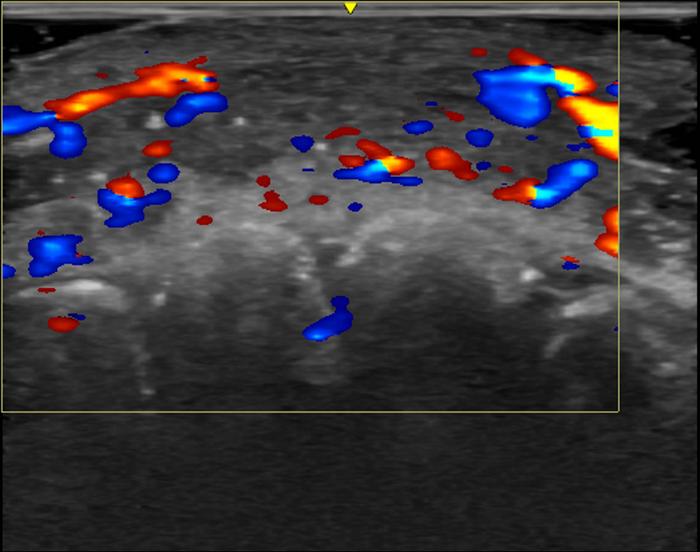

Vascular occlusion—the disruption of blood flow in arteries—on ultrasound from hyaluronic acid fillers. This ultrasound image shows absent blood flow in a segment of an artery of the lip.

Rosa Maria Silveira Sigrist, M.D., and RSNA